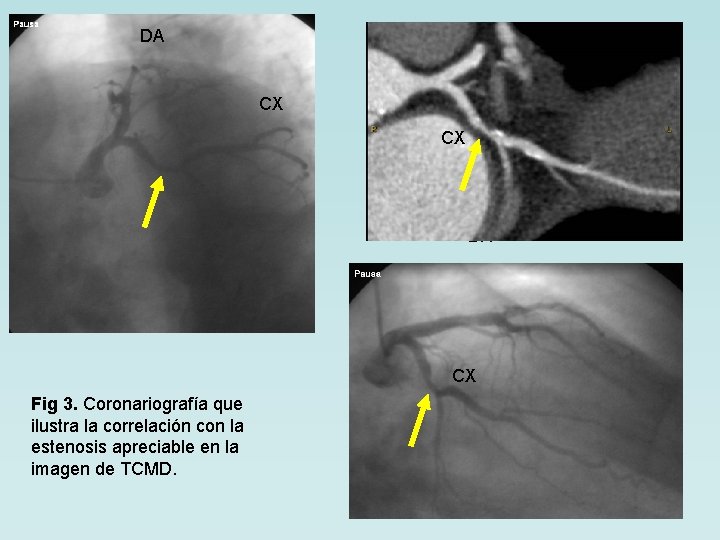

DA CX CX DA CX Fig 3. Coronariografía que ilustra la correlación con la estenosis apreciable en la imagen de TCMD.